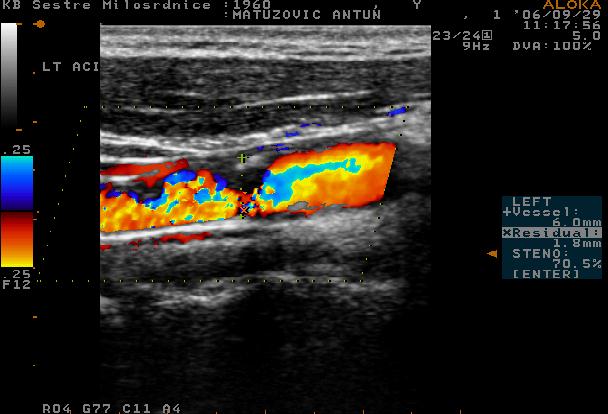

A 46-year-old male was admitted to hospital one month after he had experienced pain in the right side of the neck. Some days later he had noticed choreatic movements of his left arm. He had no history of recent trauma. Clinical neurological status revealed choreatic movements of the left arm, dysarthria, gait disturbance and psychomotor restlessness. The findings of Huntington’s chorea tests and Wilson’s disease tests were normal. MSCT scan of the brain showed signs of older infarction leasons in the right n. caudatus and calcifications in both globi pallidi (Figure 1). Extracranial colour coded sonography of the right carotid artery showed a hypoechogenic area within the proximal part of the artery lumen; and absence of color-coded blood flow presumed to be a haematoma (Figure 2). The distal part revealed double lumen of the vessel with «blunted» haemodynamics in real lumen and reversed blood flow in false lumen. Left carotid artery was sub-totally stenosed (Figure 3). MSCT angiography and DSA demonstrated almost total occlusion of the right internal carotid artery and double lumen of left internal carotid artery as a sign of dissection (Figure 4).